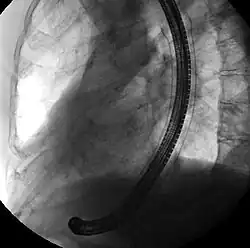

Fluoroscopic image of self-expandable metallic stent in the esophagus. The black solid structure is the endoscope used to place the stent.

Self-expandable metallic stents are typically inserted at the time of endoscopy, usually with assistance with fluoroscopy or x-ray images taken to guide placement. Prior to the development of SEMS small enough to pass through the channel of the endoscopy, SEMS were deployed using fluoroscopy alone.[13]

Esophageal SEMS are placed after a gastroscopy is performed to identify the area of narrowing. The area may need to be dilated to allow the gastroscope to pass.[14] The tumour is usually better seen with the direct vision of endoscopy than on a fluoroscopic image. As a result, radio-opaque markers are usually placed on the surface of the patient to mark the area of narrowing on fluoroscopy. The SEMS is placed through the channel of the endoscope into the esophagus over a guidewire, marked on fluoroscopy, and mechanically deployed (using a device that sits outside of the endoscope) such that it expands when in position. Hypaque or other water-soluble dye may be placed through the passage to ensure patency of the stent on fluoroscopy.[15] Enteric and colonic SEMS are inserted in a similar fashion, but in the duodenum and colon respectively.[16]